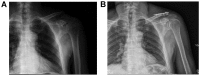

Figure 1.

Male, 44 years of age, with closed fracture of right distal clavicle caused by falling injury. (A) Preoperative clavicular radiography shows Craig class II type II fracture of left distal clavicle. (B) The clavicular radiography at 3 days after operation shows that the fracture was fixed with an anatomic plate of distal clavicle.